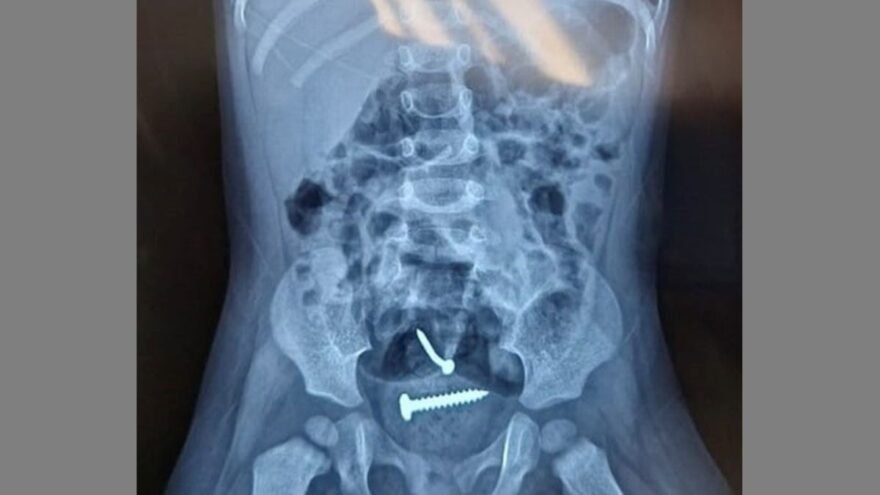

A Capitã da 2° Companhia do 12° BPM de Pedro II, Sharlene Uchôa, em entrevista, revelou que A.F.T. já havia sido preso quatro vezes, sendo uma delas na quarta-feira passada (13/12), quando foi solto pela 1° Vara da Comarca de Pedro II após ser acusado por violência doméstica. A filha de apenas um ano foi conduzida com urgência ao Hospital de Urgência de Teresina (HUT), onde um exame de raio-x identificou a presença de um objeto semelhante a um parafuso. A suspeita, conforme a investigação, é de que tenha sido o próprio pai quem introduziu o objeto.

A Capitã também informou que a criança apresenta ferimentos na região genital e está em risco de vida devido ao objeto inserido. O pai encontra-se detido na Delegacia de Polícia Civil de Pedro II, à disposição da justiça. (pensarpiaui)